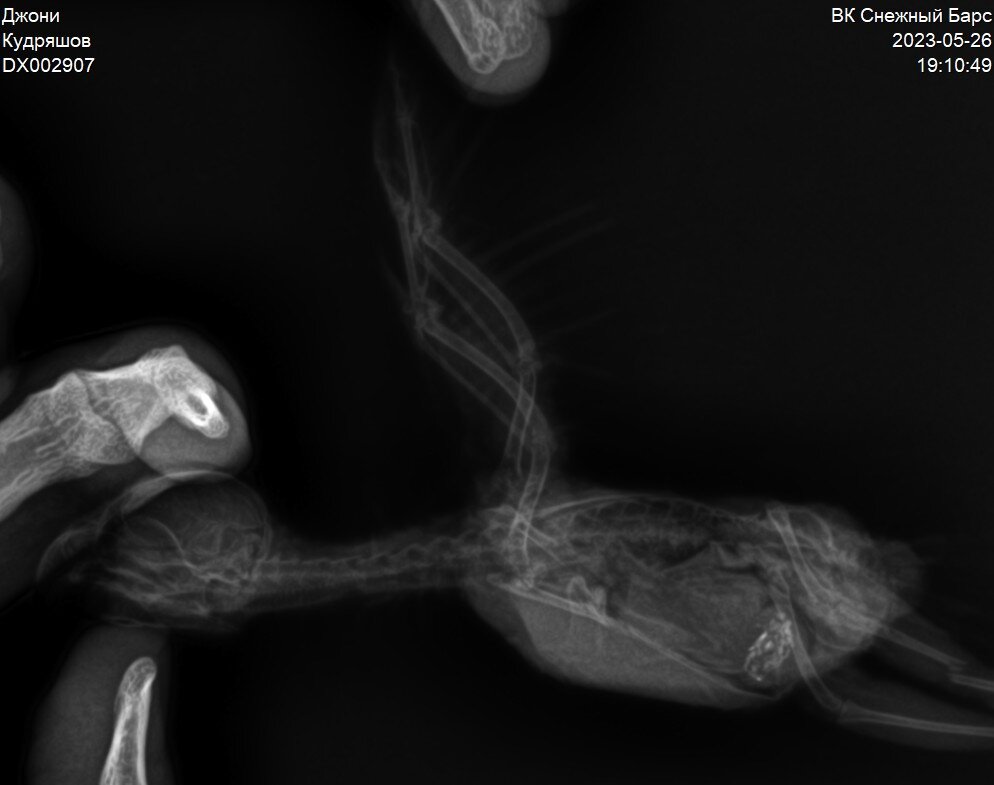

Джонни НЕРАЗЛУЧНИК

Джонни сломал лапку

Видите перелом на правой ножке?